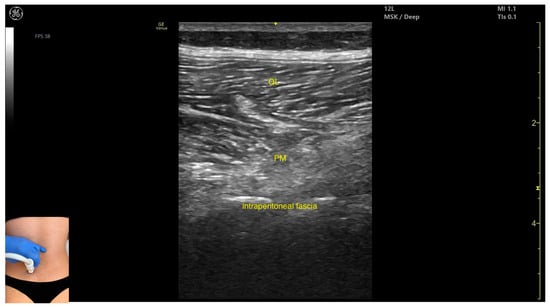

3.3.2. Ultrasound Identification

3.3.3. Key Ultrasound Landmarks

- Muscle position: It is the deepest muscle mass at this level.

- External fascia: It presents a pronounced fascia that separates it from the erector spinae and quadratus lumborum, aiding in safe botulinum toxin injection.

- Dynamic evaluation: During dynamic evaluation, when scanning proximo-medially toward the costal arch, its origin is visualized from the T12 to L5 vertebrae.

- Contraction is visible during hip flexion, as well as lumbar spine flexion and lateral inflection maneuvers.

- The psoas major can also be visualized using a longitudinal transducer position, placed superior to the iliac crest and 2 cm lateral to the L4 spinous process. In this view, both the psoas major and the overlying quadratus lumborum are seen superficial to the intraperitoneal space.

| Psoas Major | 2 cm lateral to L4 spinous process; 1 cm proximal to the iliac crest | Erector spinae muscles; quadratus lumborum (superficial); intraperitoneal space (deep to the muscle) | Transverse or longitudinal scan on posterior trunk | Avoid intraperitoneal space; inject only when muscle is clearly visualized |